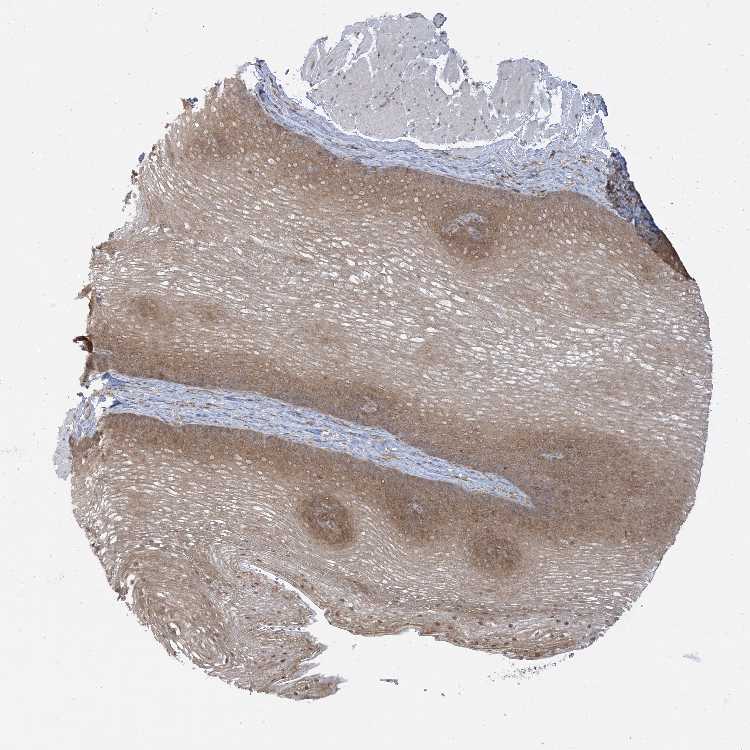

ESOPHAGUS - Antibody stainingi

Antibody staining in the annotated cell types in the current human tissue is reported as not detected, low, medium, or high, based on conventional immunohistochemistry profiling in selected tissues. This score is based on the combination of the staining intensity and fraction of stained cells.

Each image is clickable and will lead to virtual microscopy that enables deeper exploration of all samples and also displays staining intensity scores, fraction scores and subcellular localization as well as patient and tissue information for each sample.

Antibody HPA027588Antibody CAB037167

Squamous epithelial cells MediumHigh